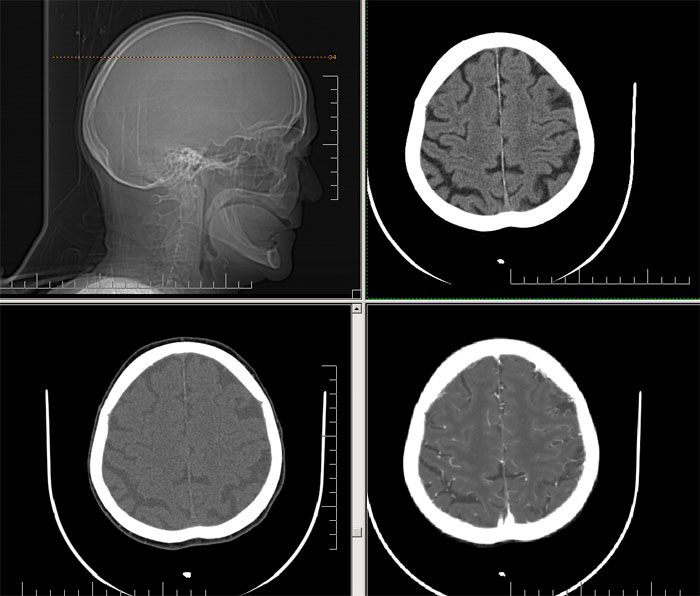

Est ce que qqun a des coupes axiales de crâne pour m'aider à réviser mon anatomie. Merci

Pour compléter tes révisions, Poupette vient de nous faire parvenir ces planches bien utiles: Planches de coupes axiales cérébrales, dans la rubrique COURS / ANATOMIE